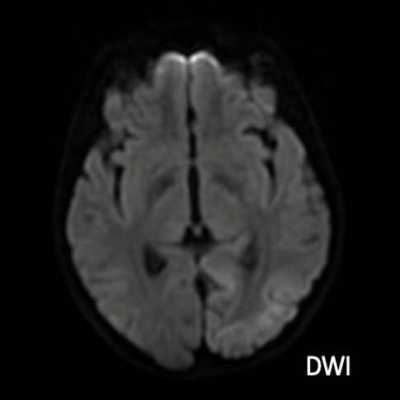

- A) Aksiyel FLAIR görüntülerde parietooksipital lobda kortikal hiperintensite (ok) ve difüzyon görüntülerde kısıtlanma alanları izleniyor (oklar). Ertesi gün çekilen kontrol MRG’de FLAIR serilerde yeni gelişen oksipital bölgede kortikal hiperintensite (ok) izlenmektedir.

- MRG’de akut fazda T2/FLAIR hiperintensiteyle birlikte giral şişme ile karakterize enfarkt-benzeri lezyonlar ve subkortikal beyaz cevher tutulumu görülür. DWI’da artmış sinyal dikkat çekmekle birlikte ADC değerlerinin normal ya da hafif artmış olması, baskın sürecin vazojenik ödem olduğunu gösterir.